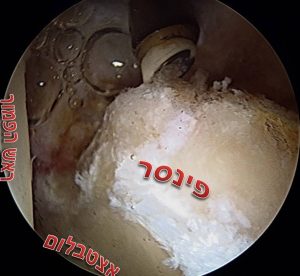

את הלברום משחזרים בעזרת שתל גיד שמוכנס למפרק דרך הפורטלים של הניתוח ומקובע למקומו בעזרת עוגנים באותו האופן שבו מתקנים לברום מקורי. שתל הגיד יכול להיות מתורם או שתל גיד עצמי (אלוגרפט או אוטוגרפט בהתאמה), באופן כללי עדיף להשתמש בשתל גיד מתורם על מנת להמנע מסיבוכים עקב הפרוצדורה לקצירת הגיד. עד לא מזמן, החלק המסובך ביותר בניתוח היה מדידת האורך של האזור שחסר בו לברום וזאת לצורך הכנת שתל בגודל מתאים, בשיטות העדכניות משתמשים בשתל גיד ארוך מראש ובסיום הפרוצדורה חותכים את השארית כך שנעשה שימוש באורך מדוייק של גיד. בעיה נוספת שהיה צורך לפתור היא נקודת החיבור בין הלברום המשוחזר לזה הקיים, לבעיה הזו פותחו שני פתרונות – האחד להחליף את הלברום כולו והשני לשמור רקמה ככל שניתן בלברום הקיים ולאחר ההשתלה לבצע חפיפה בין הלברום החדש לישן.